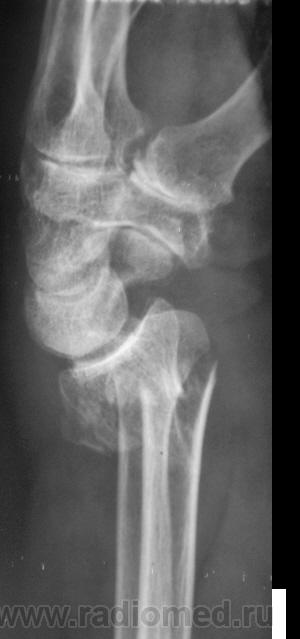

Случай 3. Пациент направлен врачом хирургом на рентгенографию лучезапястного сустава.